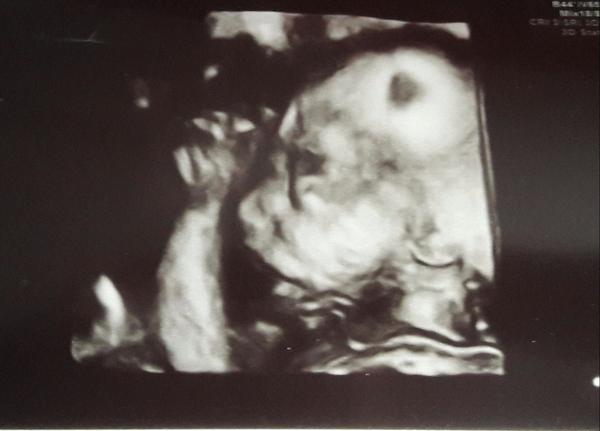

Robí aj 3D a okrem iného sa špecializuje na vyvinove vady, a je/aj bol/ detsky kardiolog. Vacsina deti s postihnutim ma nejaky problem so srdieckom

Si objednana na cas, je to tam naozaj vybavene, na partnerov su zvyknuti, ste v miestnosti kde bude zhasnute svetlo, pred Vami tá obrovská obrazovka a vidite Vase dietatko v celej krase. Da sa urobit z toho aj CD aj si kupit obrazok zo zaznamu.

Ja som bola unho dvakrát a podla mna to stoji urcite za to. mala som aj vymenny listok lebo vzdy som mala dake zle tripple testy. A aj ked som bola na morfo (2D) vzdy robil aj 3D. Vzdy kontroluje aj prietoky a vidite Vase babo aj v 3D.